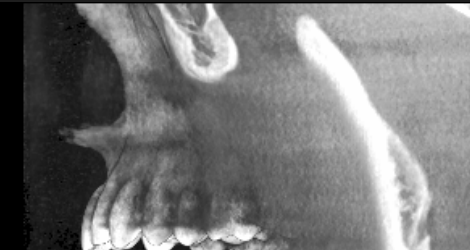

this is my x-ray, take away from here is that my ANS is projected AF.

is this usually good thing?